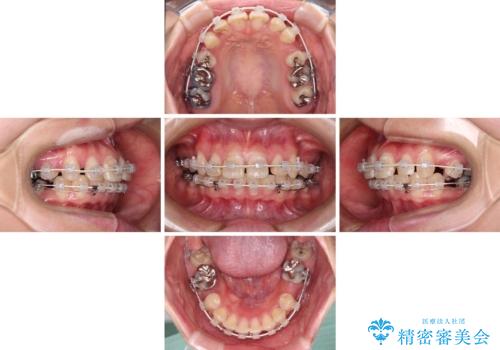

- 上の前歯の出っ歯とでこぼこの歯並びを気にして来院された患者様です。

上下顎歯列ともに前方に突出していましたが、上顎歯列がより前方位にあったため、上顎左右は第1小臼歯を、下顎左右は第二小臼歯を抜歯することとしました。

目立たないワイヤー装置にて抜歯矯正を行うこととしました。